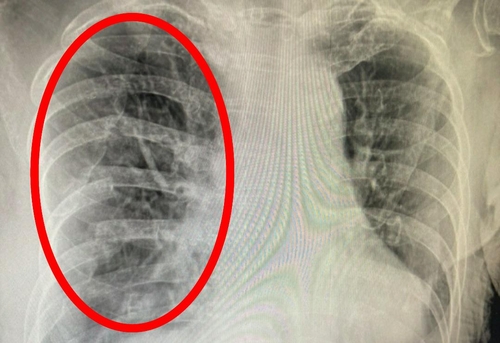

숨 쉴 때 곤란함과 갈비뼈, 가슴의 압박감, 답답함 등은 물론 잦은 기침, 쌕쌕거리는 숨소리 등이 있다고 한다면 폐 질환을 생각해 보아야 하는데 엑스레이 등으로 폐의 컨디션을 체크해 보는 것이 중요 해요 특히나체중의 감소와 같이 과도한 기침이 3주 이상 진행되었을 경우이라면 폐결핵, 기흉, 폐암 등을 확인해 볼 필요가 있어요.